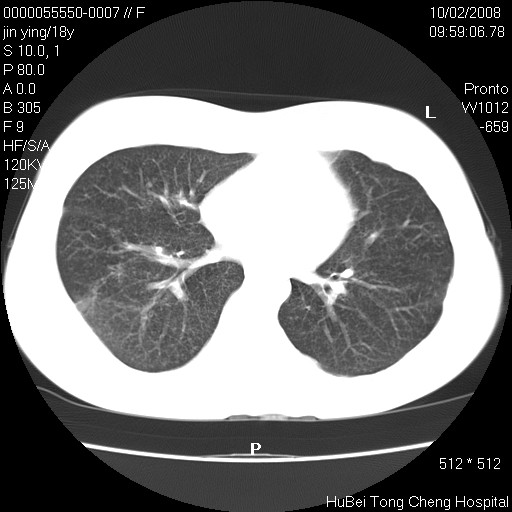

患者 女,18y。发热十余天,伴咳嗽。pe:t39⒈℃,bp 110/80mmhg,p 86次/min。神清,精神欠佳。双肺可闻及少许湿罗音。既往史不详。

临床诊断:肺部感染?

胸部ct轴位平扫(层厚10mm,螺距1.5,重建间隔10mm),图像如下: